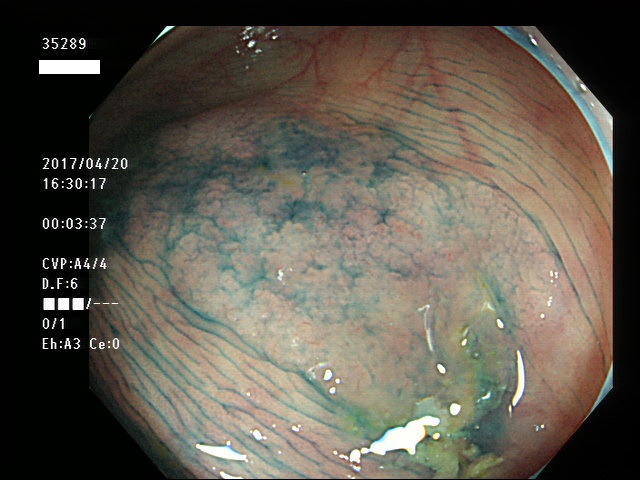

上記100名より抽出した平坦・陥凹型腺腫・SSAP(=癌化の危険が高いが見落としやすい病変)の内視鏡写真